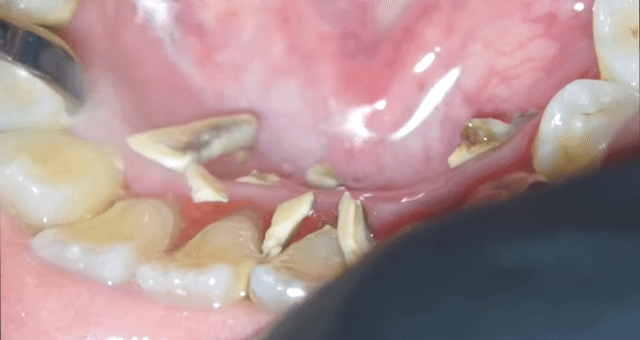

[스크랩] [흥미돋]■ 치과 스케일링 ( 치석 제거)

• 작성자한능검타파 | 작성시간 25.03.13 아 재밌어보이는데... 너무 심하셔서 ㅠ 뿌리가 보일거같아서 안타깝ㅜ

• 작성자박용희 | 작성시간 25.03.13 저정도면 진짜.. 이가 반 정도 빠진만큼 아프겄어

• 작성자촥촥한딸기케이크 | 작성시간 25.03.13 저만큼 쌓일려면 얼마나 안한거야